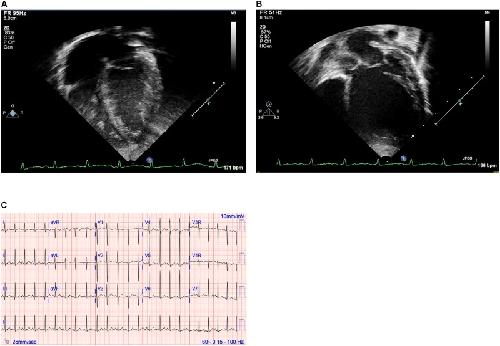

Quantitative Phenotyping of Xenopus Embryonic Heart Pathophysiology Using Hemoglobin Contrast Subtraction Angiography to Screen Human Cardiomyopathies., Deniz E, Jonas S, Khokha MK, Choma MA., Front Physiol. January 1, 2019; 10 1197. |

Familial Dilated Cardiomyopathy Associated With a Novel Combination of Compound Heterozygous TNNC1 Variants., Landim-Vieira M, Johnston JR, Ji W, Mis EK, Tijerino J, Spencer-Manzon M, Jeffries L, Hall EK, Panisello-Manterola D, Khokha MK, Deniz E, Chase PB, Lakhani SA, Pinto JR., Front Physiol. January 1, 2019; 10 1612. |